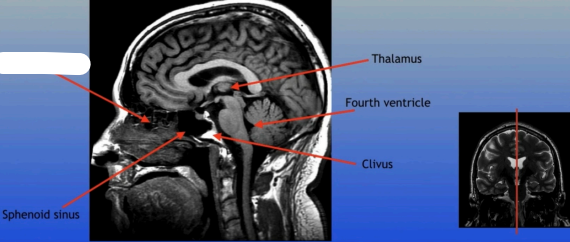

Thalamus

A large mass of gray matter located in the diencephalon, acting as a relay station for sensory information and playing a key role in regulating consciousness and sleep.

Sphenoid Sinus

Thalamus

Fourth Ventricle

Clivus

Sphenoid Sinus